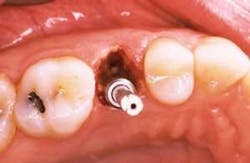

In order to preserve the extraction socket dimensions, immediate implant placement at the time of extraction has been proposed. Briefly described, the technique involves a minimally traumatic extraction of the tooth.

The appropriate implant osteotomy is carried out and the implant is then placed. Typically, the osteotomy will extend beyond the apex of the extraction socket in order to provide primary stability of the implant.

Voids between the implant and the extraction socket walls are filled using a particulate bone graft material (Figures 1 and 2).